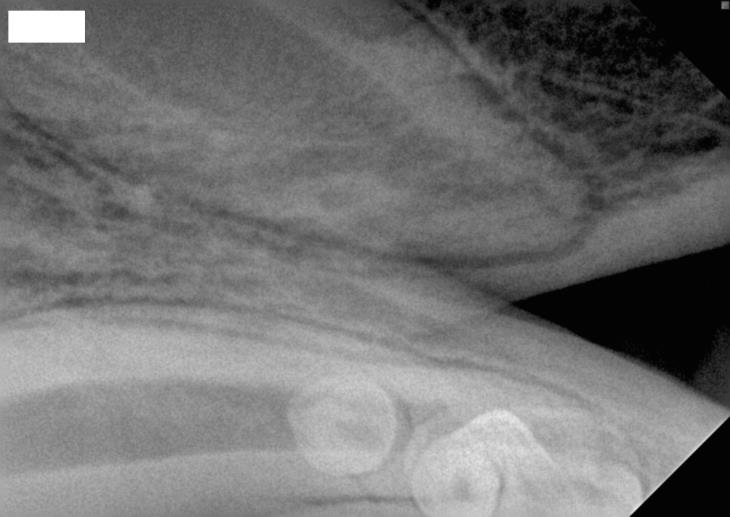

Fig 3: The same tooth seen in Image 2 four months after treatment indicating continued development of the root.